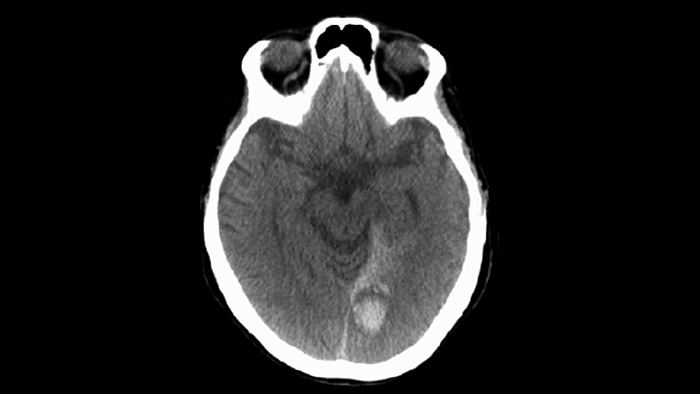

Используйте SmartCT для визуализации мягких тканей при исследовании сосудов, чтобы убедиться в успешности лечения и осуществить проверку на наличие кровотечений.

Технология ClarityIQ снижает дозу облучения на 75% при проведении DSA* для пациентов с неврологическими особенностями, создавая при этом изображения, качество которых не отличается от качества изображений системы без ClarityIQ, что является важным преимуществом при лечении большого числа пациентов. Технология автоматической компенсации артефактов движения ClarityIQ незаменима при установке устройств маленького размера в основании черепа, т. к. она подавляет артефакты черепа и движения.

Технология ClarityIQ снижает дозу облучения на 75% при проведении неврологических исследований в режиме DSA1, создавая при этом изображения, качество которых не отличается от качества изображений системы без ClarityIQ. Технология автоматической компенсации артефактов движения предоставляет ключевое преимущество при проведении процедур установки устройств маленького размера на сосуды головного мозга, т. к. стабилизирует перемещения черепной коробки и подавляет артефакты движения.